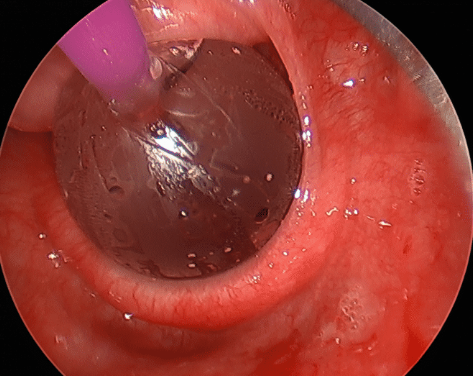

- Procedural/Surgical Treatments: (See Fig 2)

- Botulinum Toxin (Botox®) injection: Botox temporarily paralyses the muscle fibres in the CP, and possibly also effects the sensory nerve fibres, allowing better relaxation and stretching, and after 3 days, resumption of the burp reflex, and symptom resolution.

- The standard dose of Botox via this route is 75-100 Units, injected into the back½of the circular CP muscle

Fig. 2 – Multiple endoscopic injections of Botox® into back ½ of circular cricopharyngeal muscle